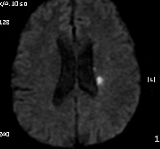

2011-9-10 근력이 G4-  로 지속, 더 이상 나빠지지는 않음. 우측 상지의 움직임이 주과적으로 둔해졌다고 하나 객관적 근력은 정상입니다. Diffusion만 촬영하였습니다.

# 손 o 일 교수님 의견

DWI coronal or saggital view 보면 분명하겠지만 이 사진으로 보니 PCA territory infarction으로 모두 설명되는 것 같습니다. PCA 영역에 hypoperfusion으로 병변이 크지는 것 같습니다. 5-7일 지나야 안정기에 들어갈 것 같습니다.